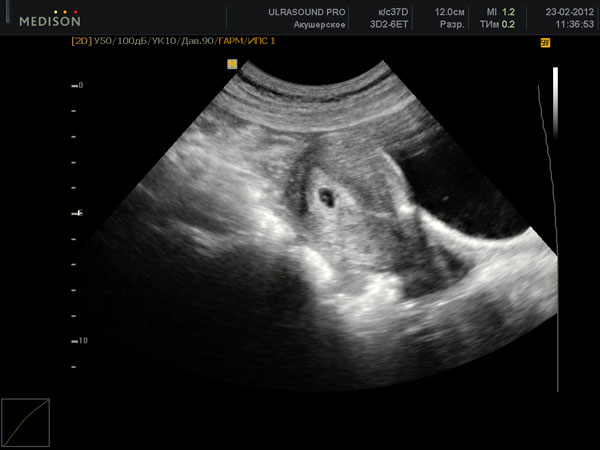

Что расскажет узи на 6 неделе беременности?

Первый триместр женщину сопровождают самые противоречивые чувства и эмоции. С одной стороны она безумно счастлива известию о своем «интересном положении», но с другой –...